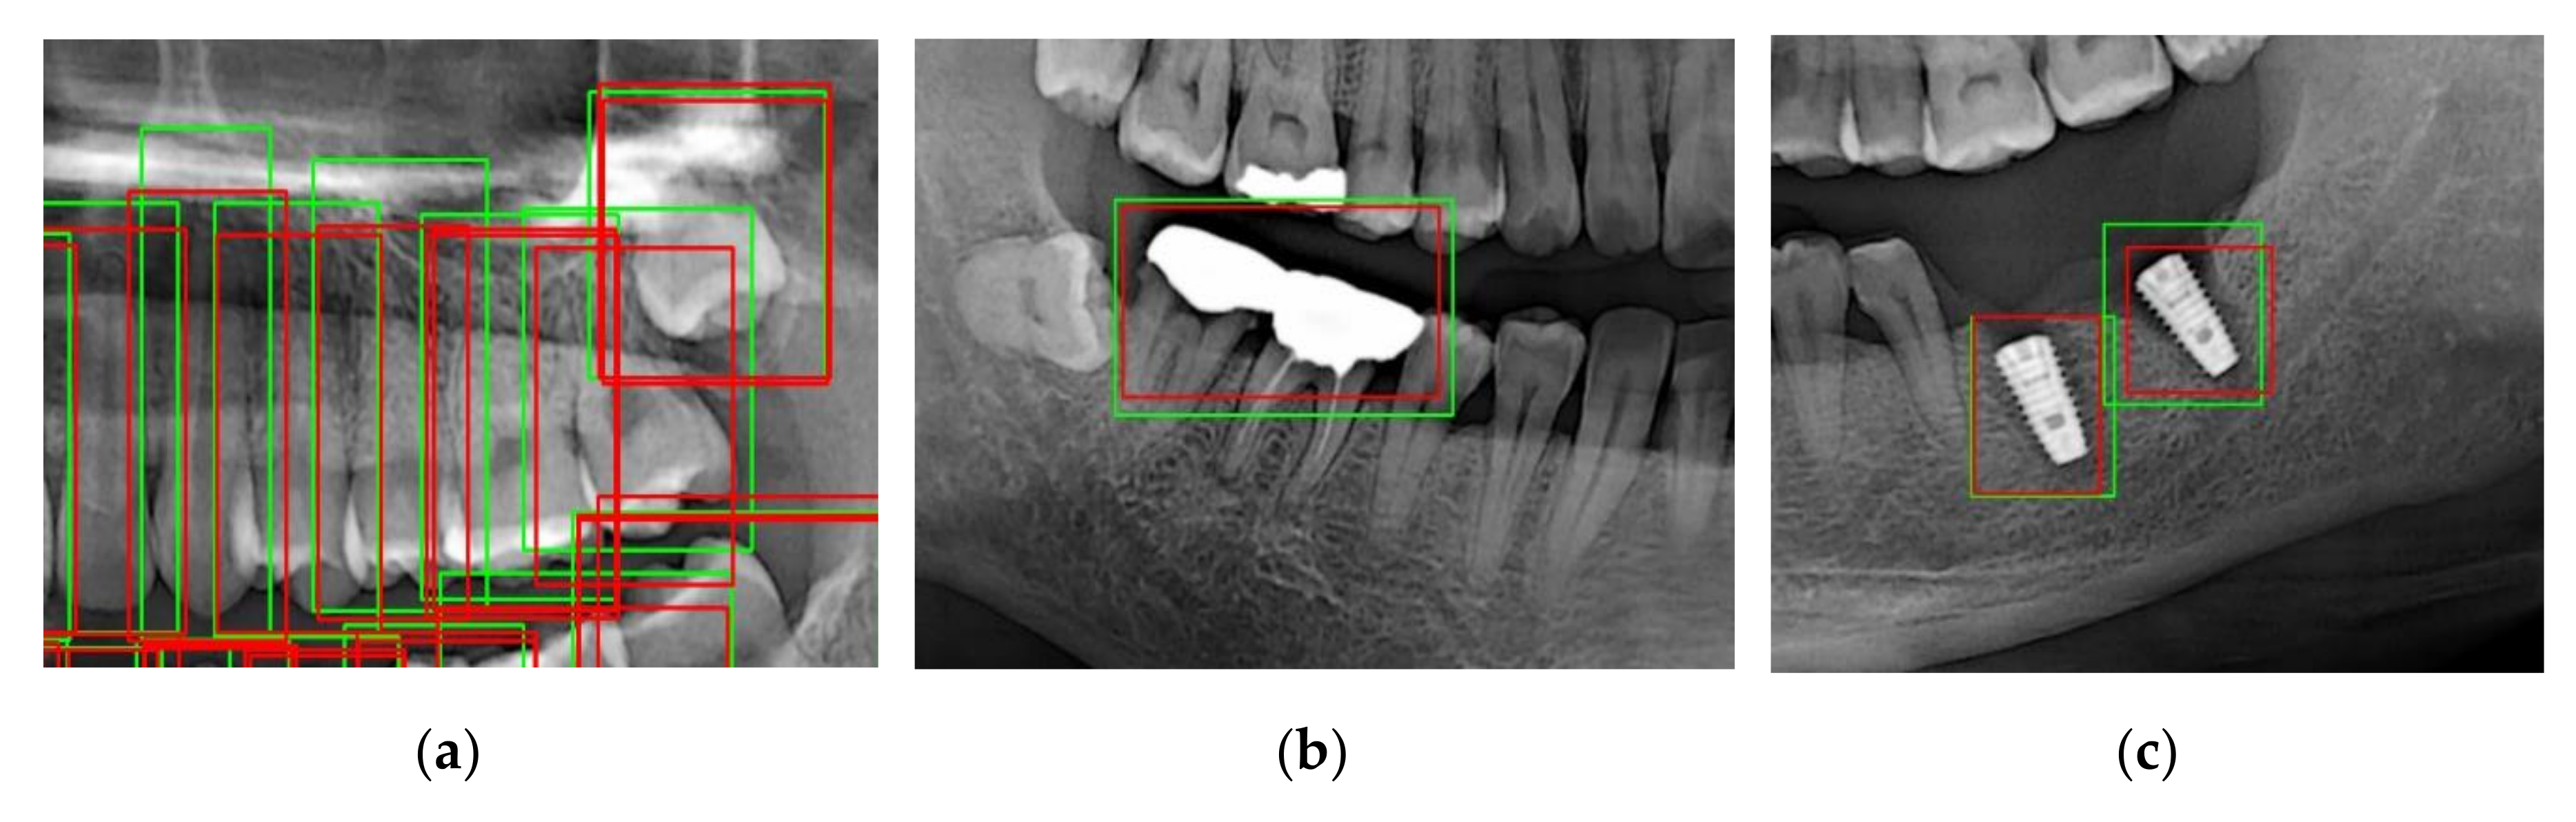

By contrast, for the case of implant fixtures and crowns, the accuracies were 45.1% and 50.9%, respectively, as shown in Table 2 when IOU = 0.5. Further, at IOU = 0.7, low accuracies of 26.6% and 40.8% were obtained for implant fixtures and crowns, respectively. These results indicate that the shapes of the implant fixtures and crowns are detected less accurately than expected. One possible reason for this is that the crowns and implant fixtures have various unstructured shapes, and hence the model may be unable to accurately detect the shapes when compared to normal teeth. Nevertheless, the results obtained are significant because the implant fixtures and crowns were still detected through the panoramic images. Therefore, as shown in Figure 9, each tooth, implant, and crown can be detected. As described above, the numbering of the teeth, the implant, and the crown is determined by detecting the teeth.

Figure 9. (a) Example of tooth, (b) crown, and (c) implant fixture detection.